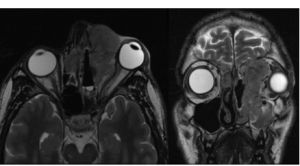

Computerized tomography (CT) and magnetic resonance imaging (MRI) are required for staging; CT provides information on bony erosion and MRI provides more accurate detail of soft tissue invasion. [10] ENB lacks a specific radiologic appearance and is seen as a homogenous soft tissue mass in the upper nasal cavity occupying the ethmoid air cells. Invasion of the cribriform plate and medial orbital walls is common and can help stage disease. [2]

All Images are courtesy of Icahn School of Medicine at Mount Sinai